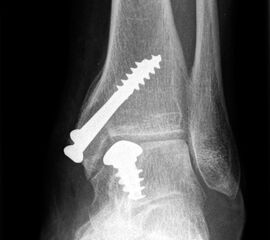

Eine vorausgehende Arthroskopie ist zu empfehlen. Zum Einbringen des Implantates ist eine Osteotomie des medialen Malleolus erforderlich.

Zum Lesen der Bildbeschreibung und zur Vollansicht bitte die Bilder anklicken. Bilder: Christoph Becher.

Abschließend erfolgt die Osteosynthese des medialen Malleolus und der schichtweise Wundverschluss. Anschließend Anlegen eines sterilen Wundverbandes sowie Ruhigstellung in einer Gipslonguette in Neutralstellung.

CAVE: Bei der postoperativen Röntgenkontrolle muss bedacht werden, dass die Knorpelschicht nicht abgebildet ist. Da das Implantat bei einer korrekten Positionierung unterhalb des Knorpelniveaus die knöcherne Fläche dennoch etwas überragt, kann dies zu einer Fehlinterpretation führen, dass das Implantat übersteht.

Zum Lesen der Bildbeschreibung und zur Vollansicht bitte die Bilder anklicken. Bilder: Sarah Ettinger.